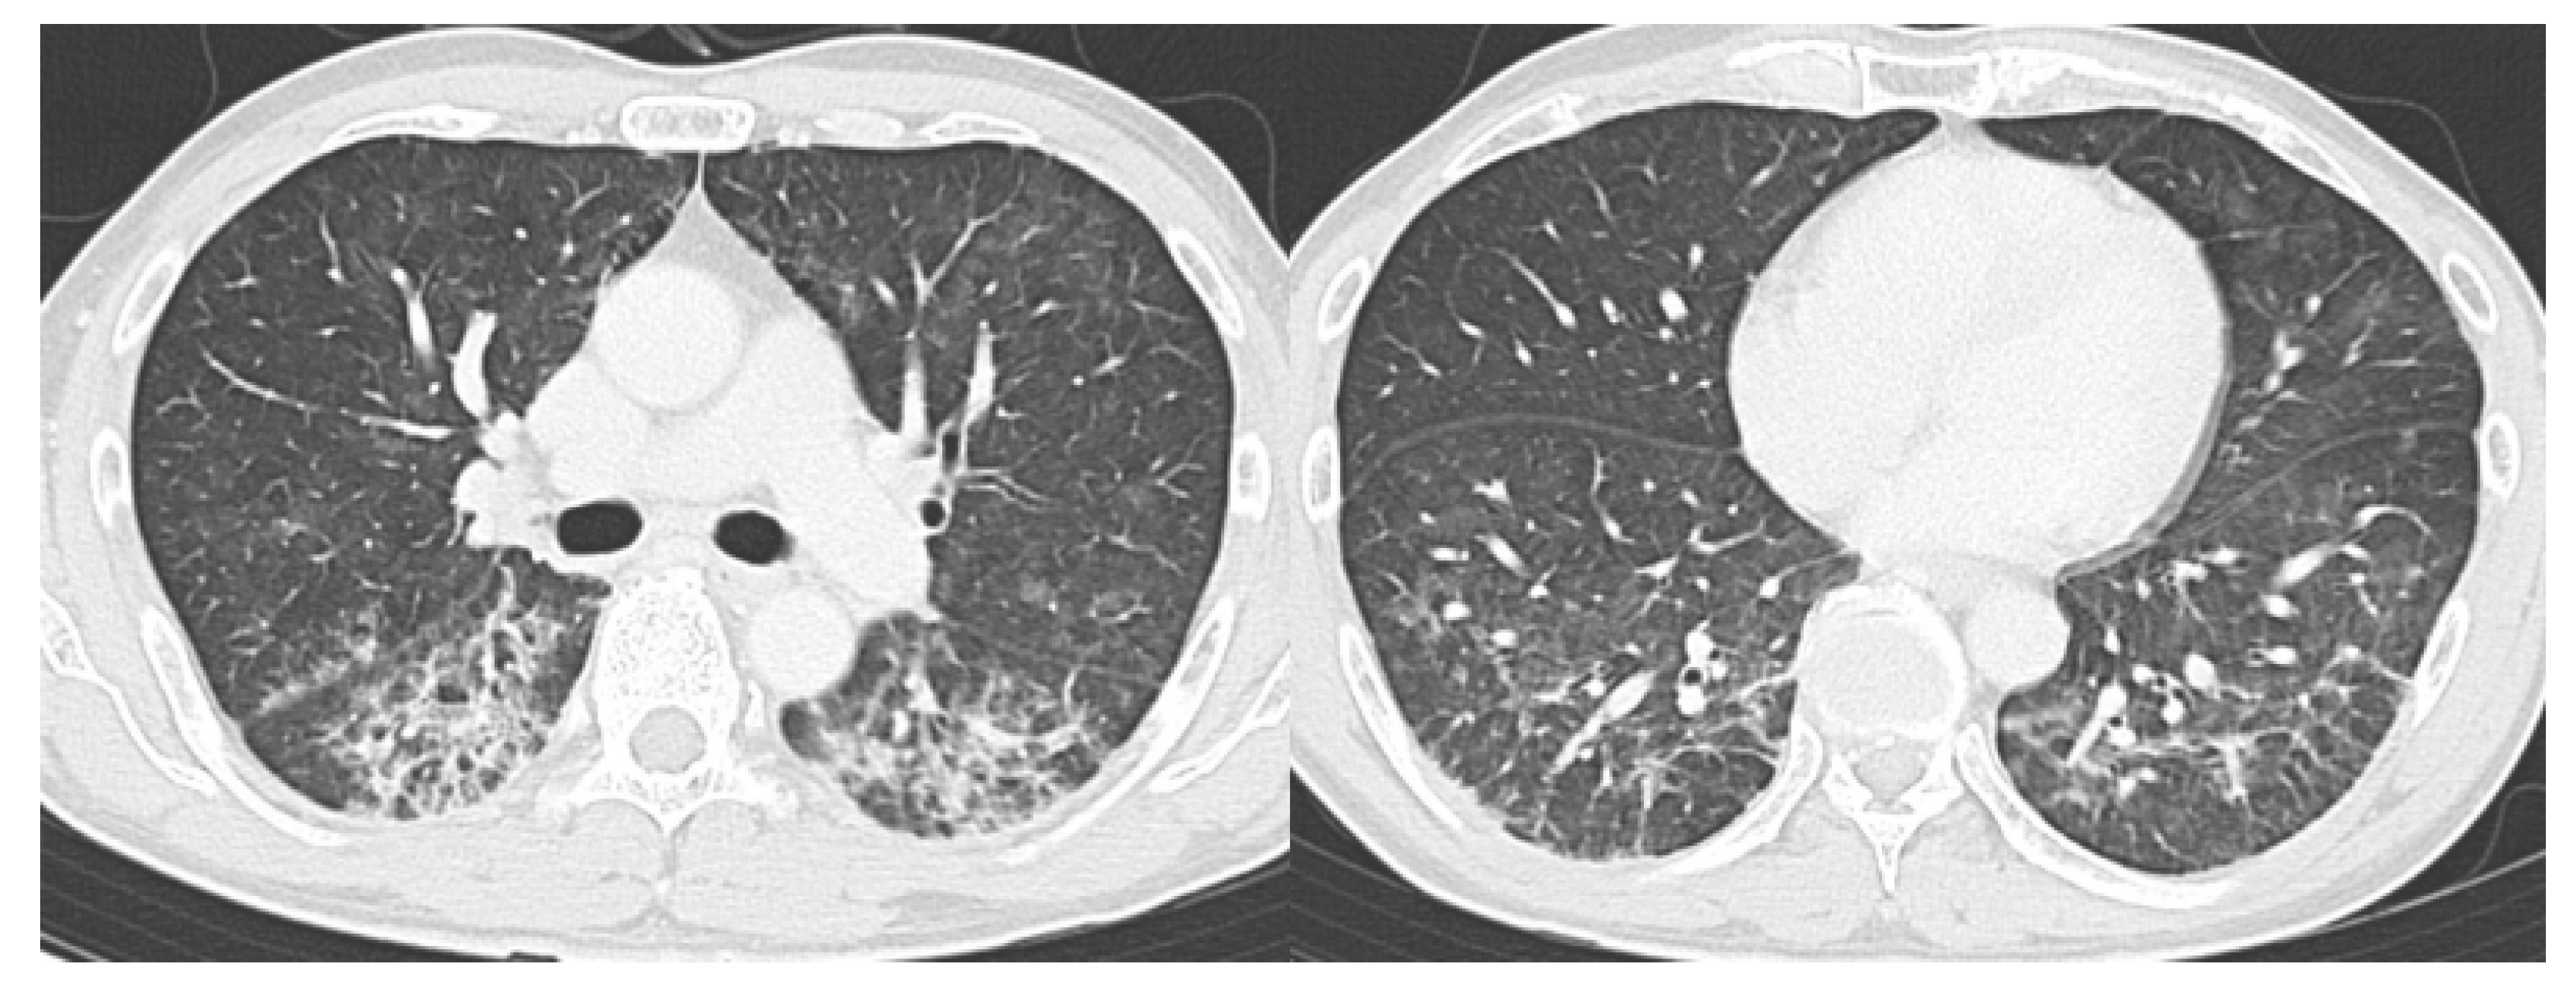

- CO-RADS 3 means CT findings equivocal for pulmonary involvement of COVID-19 that can also be seen in other types of viral pneumonia or non-infectious etiologies. Findings include perihilar ground-glass, homogenous extensive ground-glass with or without sparing of some secondary pulmonary lobules, or ground-glass together with smooth interlobular septal thickening with or without pleural effusion in the absence of other typical CT findings.

- CO-RADS 4 means a high level of suspicion for pulmonary lesion resulting from COVID-19, based on typical CT findings but exhibiting some overlap with other types of (viral) pneumonia. Findings are not located in contact with the visceral pleura or are located strictly unilaterally, have a predominantly peribronchial distribution, or overlap with severe diffuse preexisting pulmonary abnormalities.

- CO-RADS 5 means a very high level of suspicion for pulmonary lesion resulting from COVID-19, based on typical CT findings. Obligatory features are ground-glass opacities, with or without consolidations, close to visceral pleural surfaces, including the fissures, and a multifocal bilateral distribution.